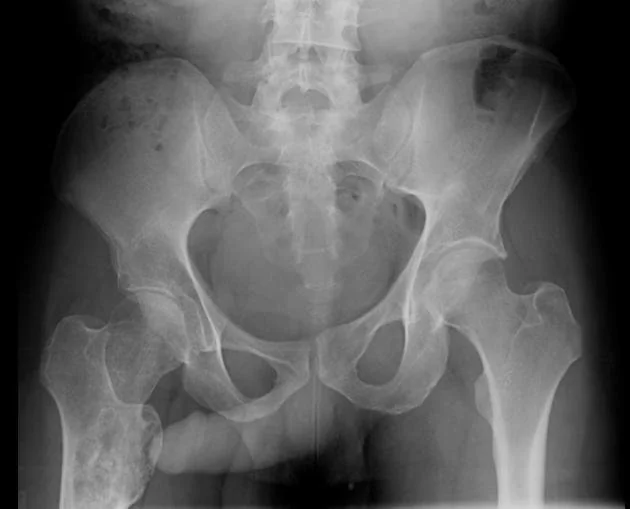

IMG20251208122511.jpg

Здравствуй двачик, сегодня мы с вами опять будем играть в рентгенолога, я вам буду постировать фоточки, а вы узнавать пиздецомы на них.

Гидроторакс с линией демуазо?

Ну чот, а метастазы чому игноришь?

>>327474857

Тут просто гидроторакс, там недостаточность по большому кругу

>>327474923

>>327475468

>>327475480

Аноним 09/12/25 Втр 08:25:44 #46 №327475571